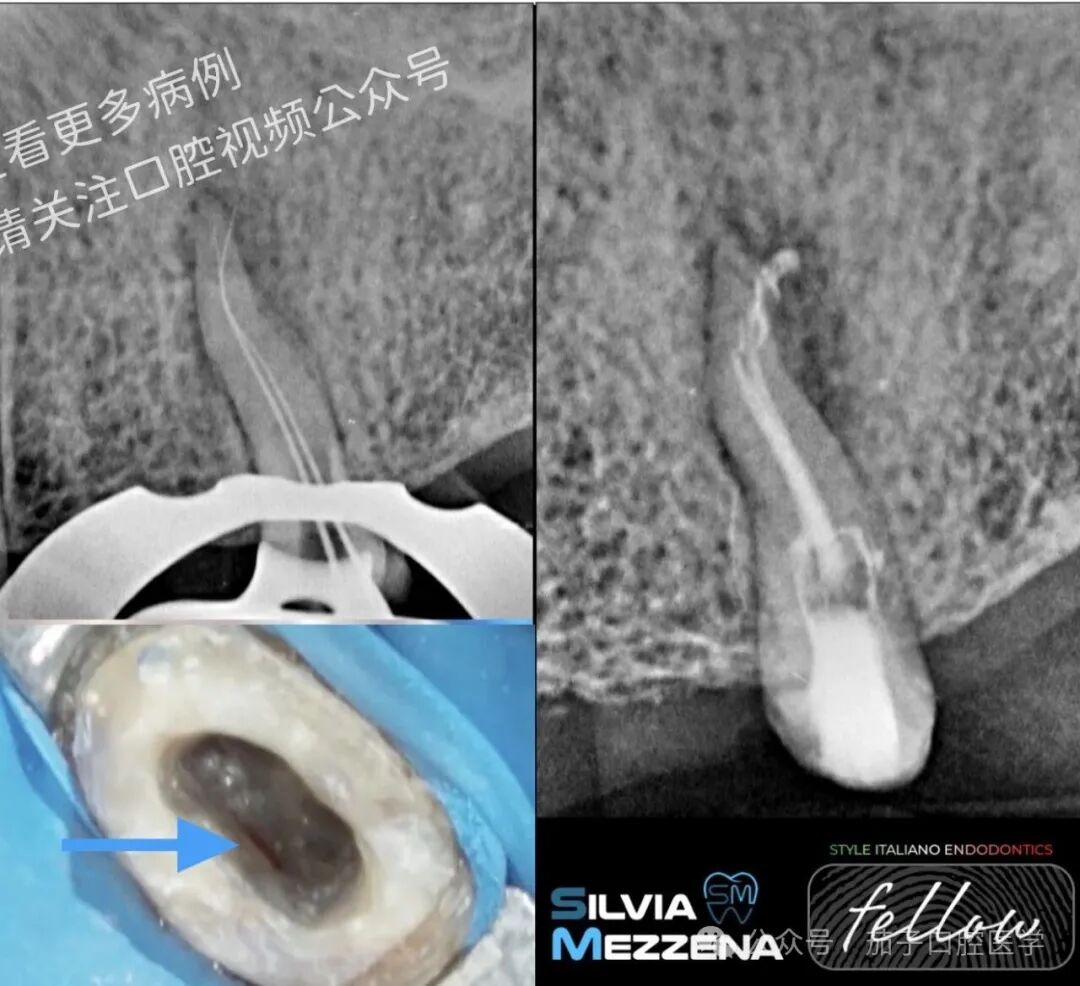

图5手术在1:50,000利多卡因局部麻醉下进行。小心翻起带近中及远中松弛切口的全厚黏骨膜瓣,以充分暴露术区。暴露皮质骨后即见肉芽组织,故未行骨切除术。清除肉芽组织后,使用Lindemann车针行根尖切除术。下图可见根尖切除后断于根内的K锉(蓝色箭头)。另可见两个根管封闭情况:颊侧根以Thermafil封闭,舌侧根内含断锉。

图6使用超声工作尖进行根尖倒预备,制备出适合预混型生物陶瓷糊剂封闭的窝洞。瓣复位后以不可吸收4-0 PTFE缝线严密缝合。患者接受全部术后及居家口腔卫生指导,包括使用0.20%氯己定漱口水联合1%氯己定牙周凝胶,每日三次,持续15天。

图7X线片显示术前与术后状况。软组织照片分别展示术后7天及30天情况。